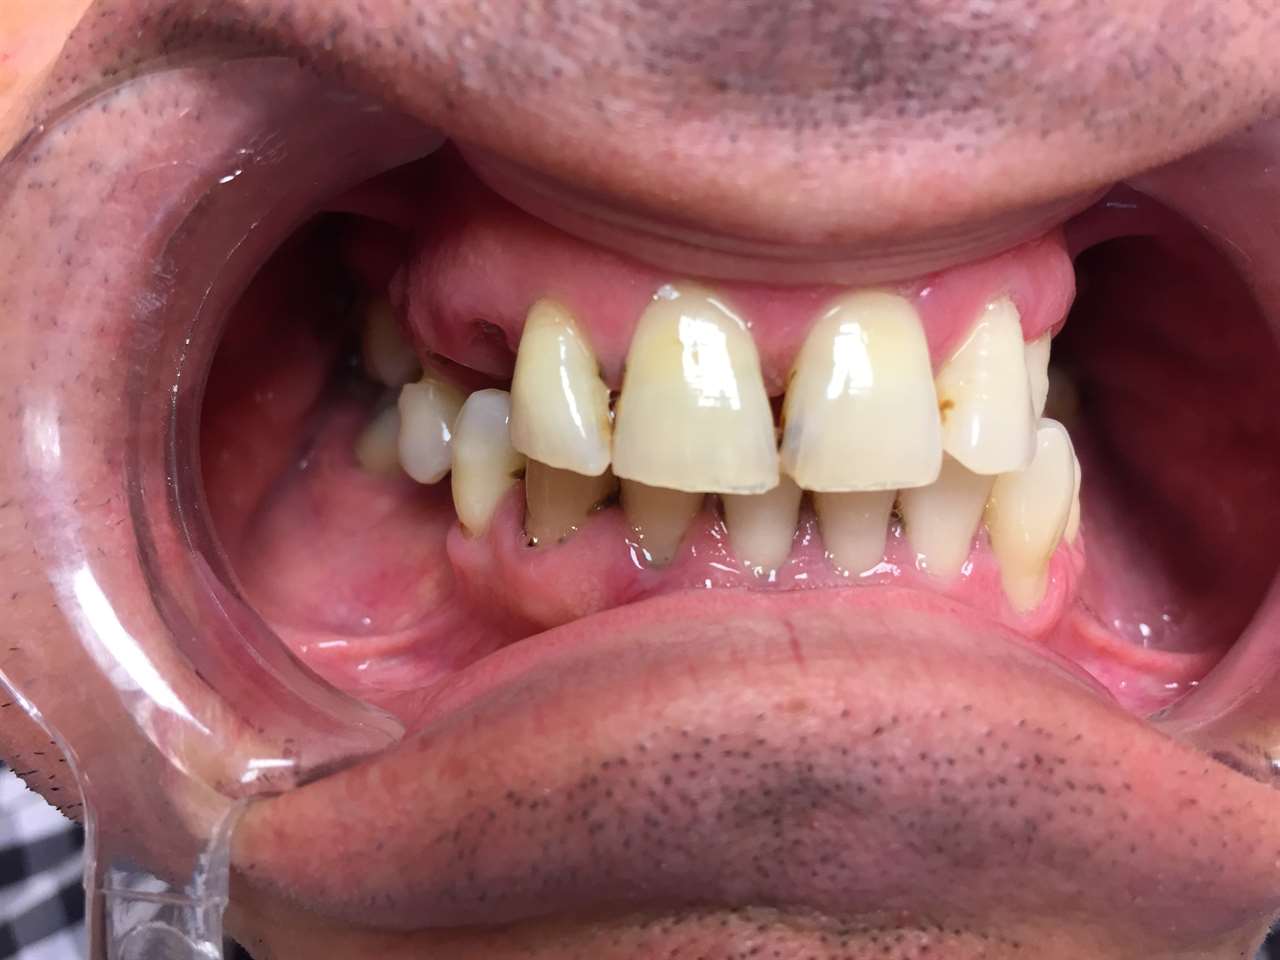

Teljes szájüregi rehabilitáció két lépésben

Ismét egy teljes szájüregi rehabilitáció két lépésben. Először az alsó fogak lettek kihúzva és azonnal implantálva, híddal ellátva, majd később a felső. IHDE svájci azonnal terhelhető implantátumok és cirkónium hidak. Dr. Kelemen Péter és a Symbion Fogtechnika közös munkája.